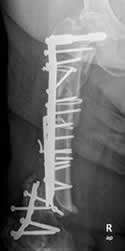

Fig 114. Aflojamiento.

A: Rx AP. Aflojamiento de la prótesis, con un espacio mayor de 2 mm. Adicionalmente hay fractura en el tercio medio del vástago. (Flecha gruesa).

B: TAC reconstrucción coronal. Aflojamiento de la prótesis.